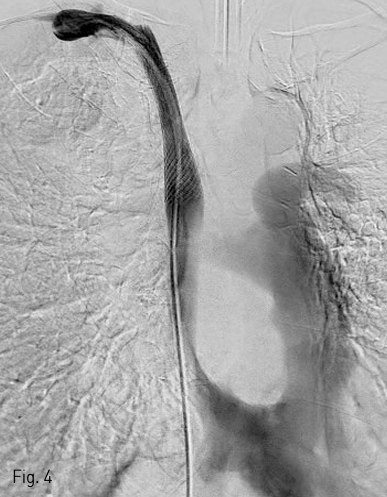

국소 마취를 시행하고 우측 대퇴정맥을 천자하여 0.035 인치 유도 철사 (Terumo, Tokyo, Japan) 와 5F C2 catheter (Cook, Bloomington, IN) 를 이용하여 catheter를 우측 쇄골하정맥에 위치시키고 시행한 정맥조영술에서 상대정맥의 협착을 확인하였다 (Fig. 1). 0.035 인치 유도철사를 따라 직경 10mm, 길이 4cm sized balloon catheter (ATB advance; Cook, Bloomington, IN) 를 삽입하여 상대정맥의 협착부위에 대해 풍선 확장술을 시행하였다 (Fig. 2). 10mm balloon으로 확장 중 waist가 발생하였으며 6 atm 시 waist가 소실되었다 (nominal pressure 5 atm, burst pressure 14 atm). 풍선 확장술 시행 후 시행한 정맥조영술에서 상대정맥에 조영제 유출과 우측 폐에 혈흉이 관찰되었다 (Fig. 3A, B). 이에 즉시 0.035 인치 유도철사를 따라 직경 10mm balloon catheter를 다시 삽입하여 조영제 유출 부위에 대해 balloon tamponade를 시행하였다. Balloon tamponade 후 시행한 정맥 조영술에서 조영제 유출의 양은 감소하였으나 지속적인 조영제 유출이 관찰되어 0.035 인치 유도철사를 따라 직경 14mm, 길이 6cm sized Wallstent (Boston scientific, Natric, MA)를 조영제 유출 부위에 설치하였다. 시술 후 시행한 정맥조영술에서 스텐트를 통한 혈류의 흐름이 원활하고 더 이상 조영제 유출이 되지 않는 것을 확인하였다 (Fig. 4). 혈흉의 치료를 위해 10.2F drainage catheter (Cook) 를 우측 흉강에 설치하였다.

Fig 4

Right subclavian venogram after stent placement shows no evidence of contrast media leakage.